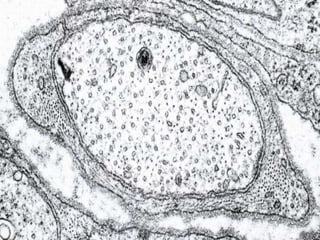

Este documento presenta imágenes microscópicas de diferentes tipos de tejidos y estructuras celulares teñidas con varios métodos histológicos. Incluye fotografías que muestran fibras de colágeno, elásticas y reticulares en diversos órganos, así como membranas basales y células especializadas de órganos como riñones, glándulas mamarias y próstata. El propósito es demostrar la aplicación de técnicas histológicas para visualizar componentes celulares y tej